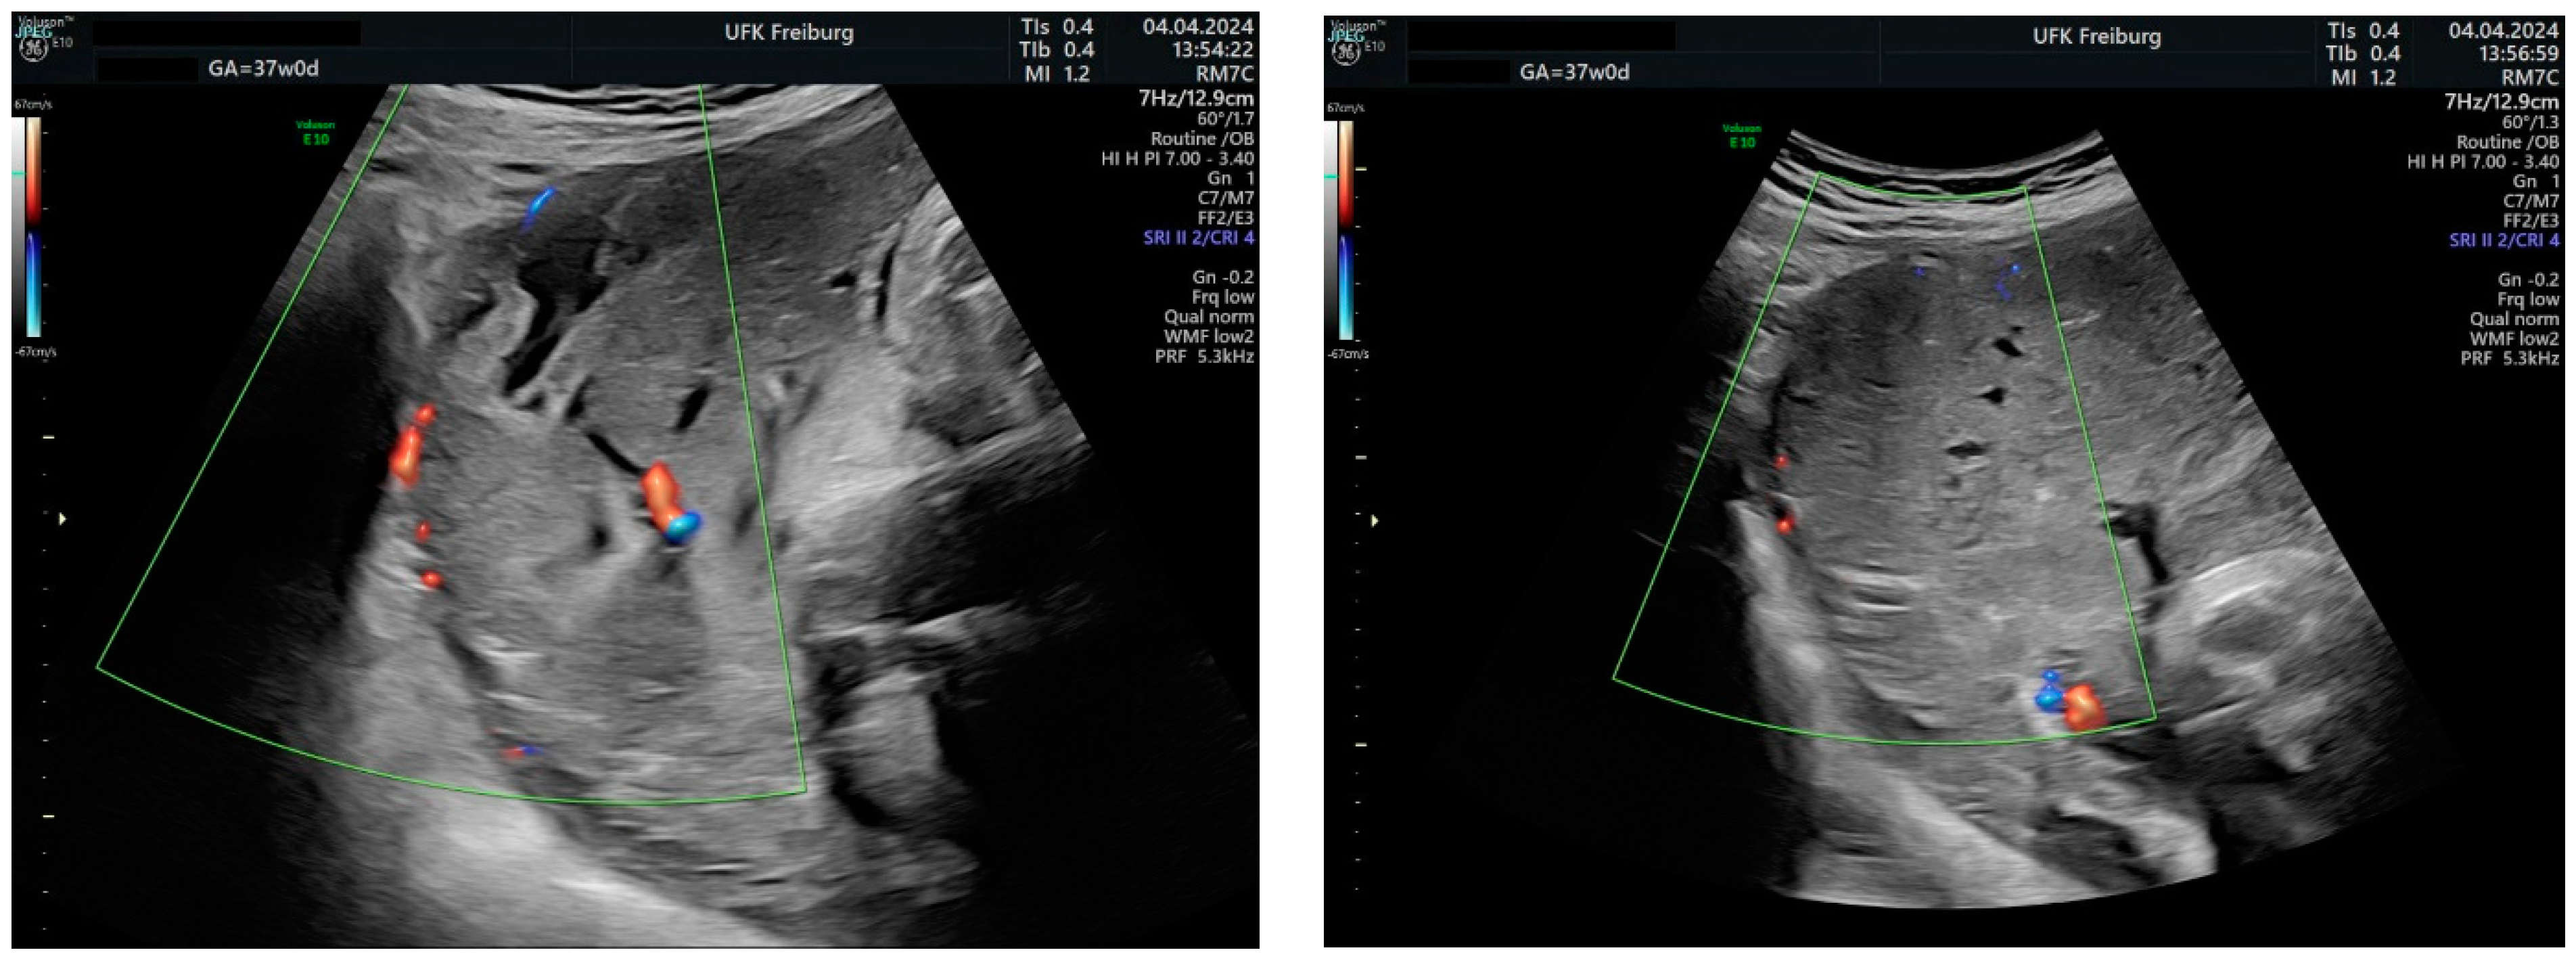

Sonographic findings (Figure 11):

Figure 11.

Increased placental blood flow on 2D ultrasound. Red color represents increased placental blood flow moving to the transducer; blue color represents placental blood flow moving leaving away from the transducer.